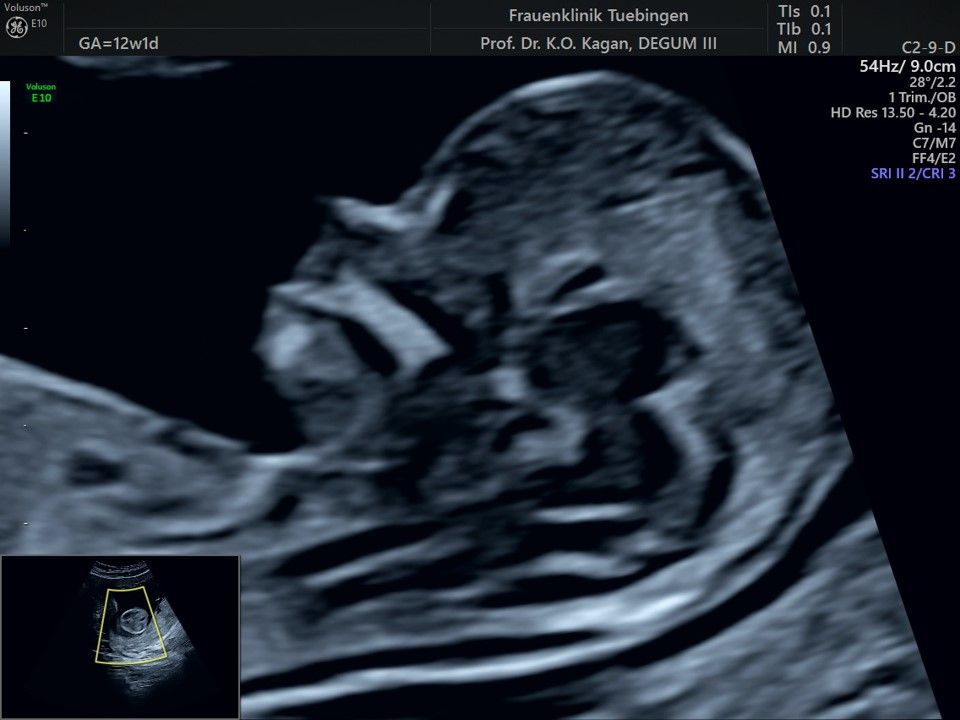

Im Rahmen des Ersttrimester-Screenings untersuchen wir die Organe des Feten mittels Ultraschall. Dabei machen wir auch gerne ein Bild für Sie.

Obwohl der Fet zu diesem Zeitpunkt erst zwischen 5 und 8cm groß ist, lassen sich bereits etwa die Hälfte aller schwerwiegenden Fehlbildungen erkennen bzw. ausschließen. Sollten wir eine Auffälligkeit sehen, werden wir mit Ihnen den Befund und das weitere Vorgehen ausführlich besprechen.

Fetale Anatomie